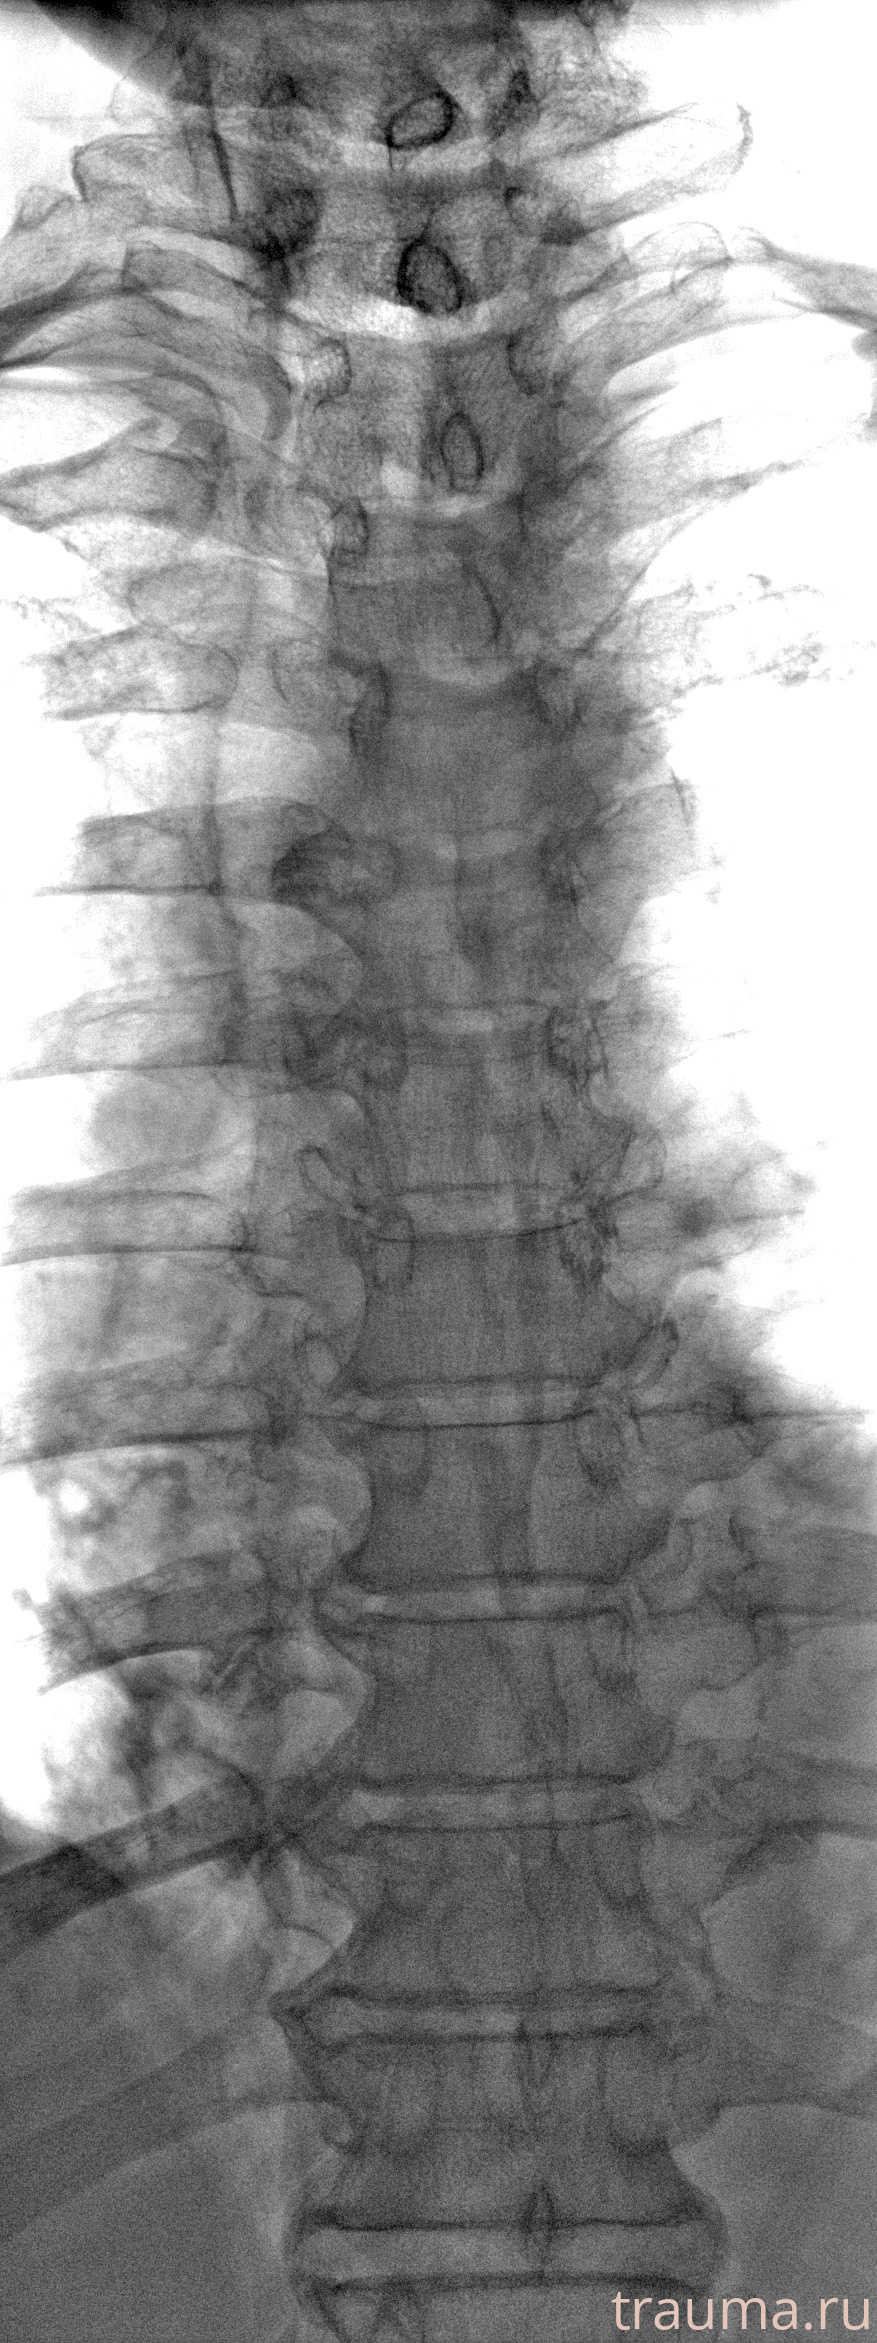

Рентген на дому: по вашему адресу приезжает врач-рентгенолог, травматолог-ортопед с мобильным рентгеновским аппаратом, проводит диагностику травмы или заболевания, делает необходимые рентгенограммы, дает рекомендации по дальнейшему лечению. Получить качественные снимки в домашних условиях возможно благодаря уникальной методике, разработанной МосРентген Центром для института  Склифосовского